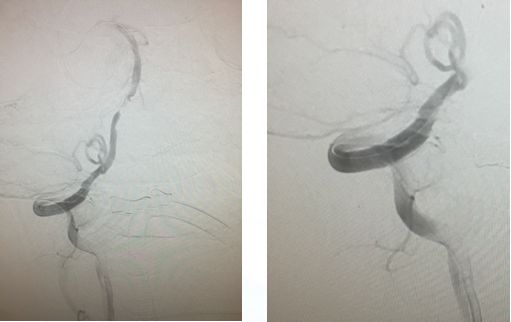

右椎入路微导管手推造影,寻找血管闭塞位置

右椎V4段狭窄,2.5*15球囊扩张(应用替罗非班)

13:40:应用3.0*13Apollo支架释放血管再通